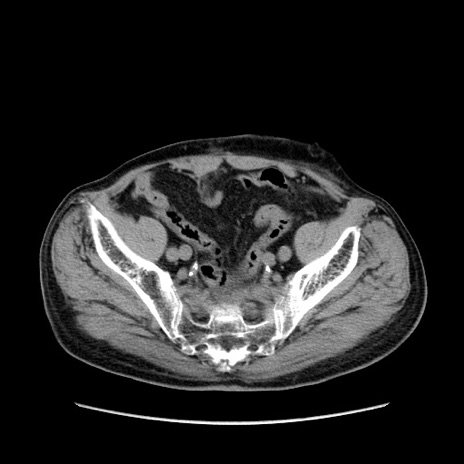

症例24(横断像)

【症例】80歳代男性

【主訴】左側腹部痛、嘔吐

【現病歴】本日早朝より左腹部に痛みあり。昼頃嘔吐認めたため、救急要請。

【既往歴】直腸癌(Mile手術)、胆摘

【身体所見】意識清明、BT 35.9℃、BP 221/93mmHg、SpO2 97%(RA) 、腹部:左ストーマ周囲に限局性の腹部膨隆あり。 膨隆部自発痛・圧痛あり・軟。

【データ】WBC 7700、CRP 0.09